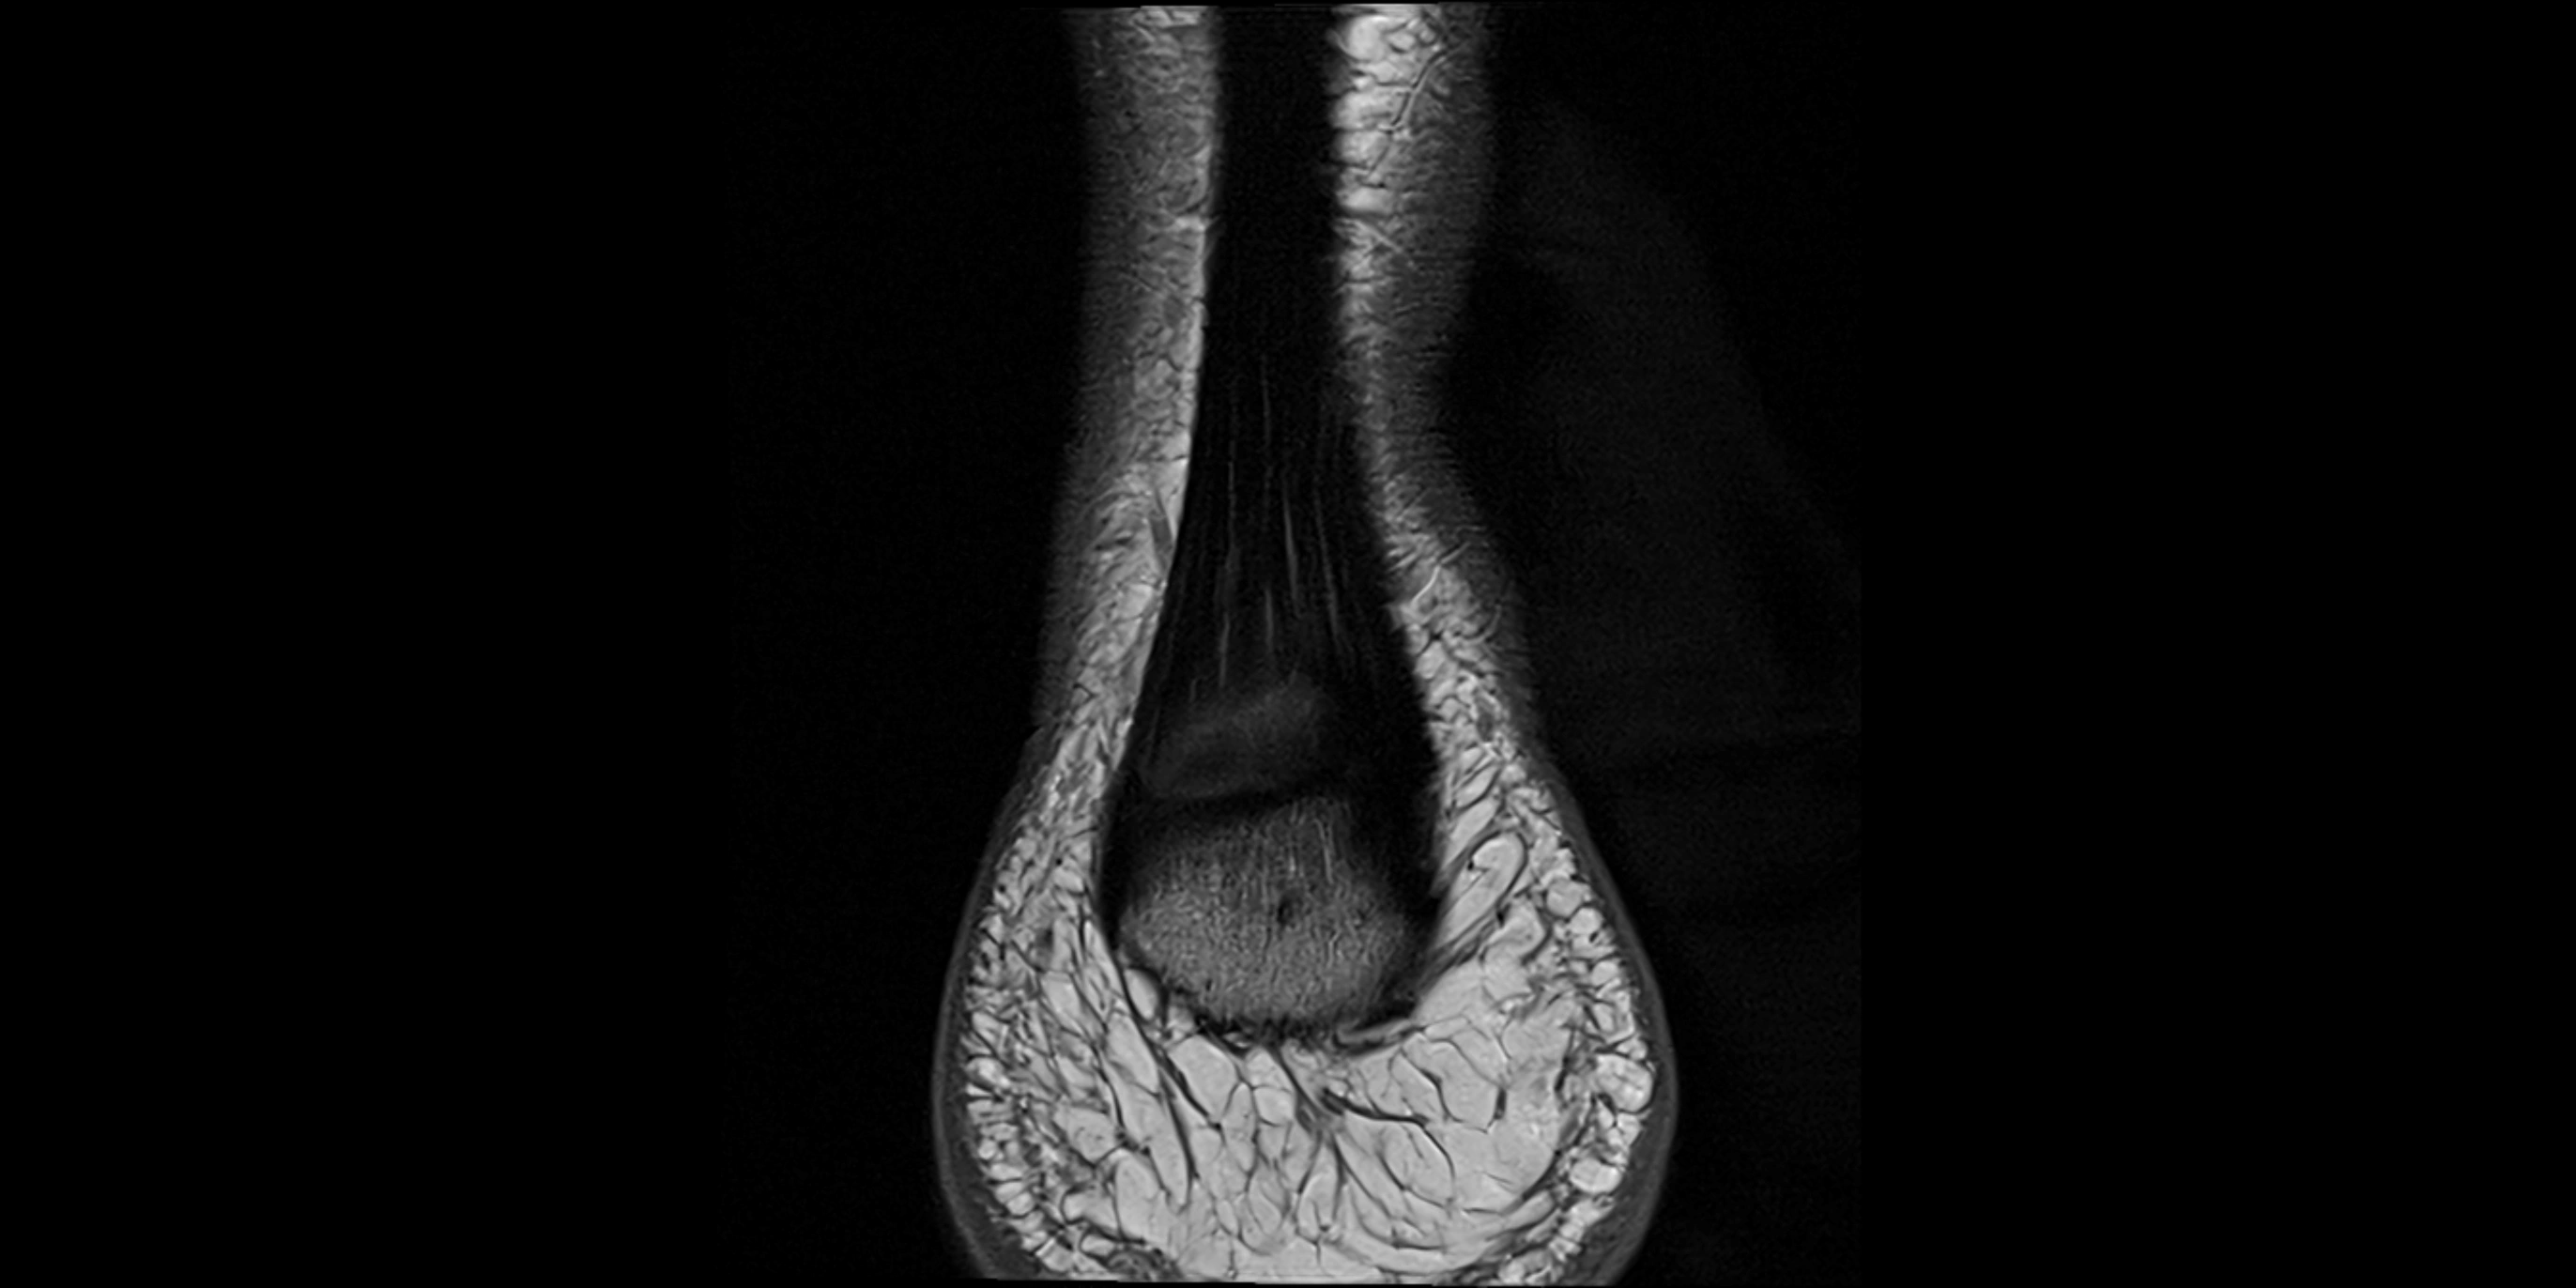

MRI image

image